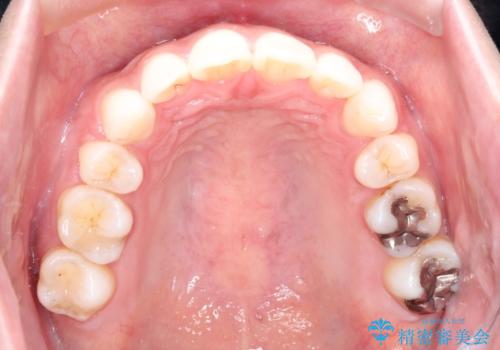

- 審美装置

- 2年1ヶ月

上下左右の歯を1本ずつ抜歯して、そのスペースを利用して口元を引っ込める計画としました。